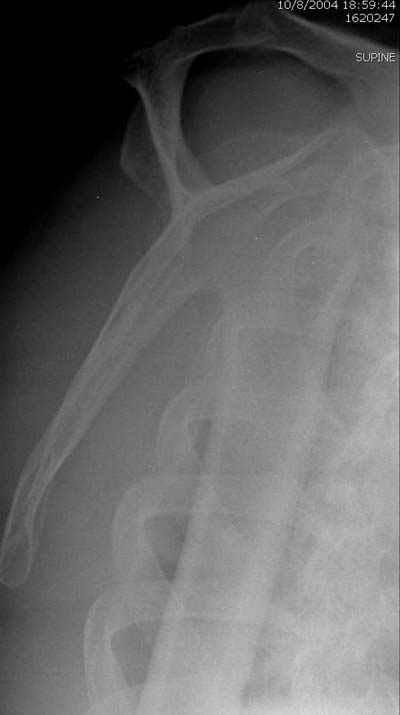

Здесь случай перелома-вывиха плеча, больному 56 лет, после "дважды" закрытой неудачной репозиции, опять же ургентно взяли в операционную, после полного общего обезболивания попытались сделать репозицию, и фиксацию провели спицами.

Больной находился в повязке, примерно напоминяющей косыночную, рекомендованы движения в локтевом суставе и маятниковые движения в плече, спицы удалены в три недели (были случаи миграции)

Больной амбулаторный, предупрежден на случай осложнения АВН головки.